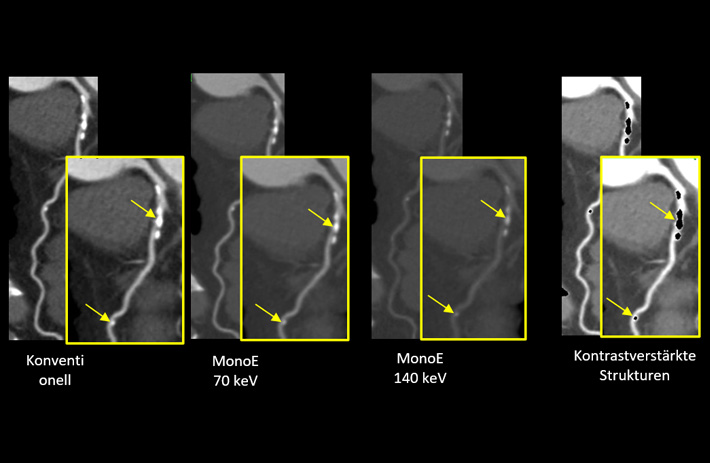

Mit dem Spektral-Detektor-CT werden Spektraldaten automatisch bei jedem Scan erfasst. Die Informationen stehen jederzeit auf der Scankonsole, der CT-Workstation sowie an jedem PACS-Arbeitsplatz zur Verfügung, sodass es nicht notwendig ist, den Patienten erneut zu scannen, bspw. wenn initial zufällige Anomalien festgestellt wurden. Dadurch profitieren Anwender durch eine höhere Diagnosesicherheit und weniger Nachuntersuchungen auf anderen bildgebenden Systemen. Unsere Fallsammlung zeigt, welchen klinischen Mehrwert der Spektral-Detektor-CT in unterschiedlichsten Anwendungsbereichen in der klinischen Routine bringt. Jede Woche gehen neue Fälle live.